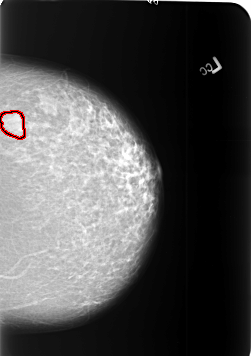

B_3405_1.RIGHT_CC

FILE: B_3405_1.RIGHT_CC.OVERLAY

TOTAL_ABNORMALITIES 1

ABNORMALITY 1

LESION_TYPE MASS SHAPE ARCHITECTURAL_DISTORTION MARGINS SPICULATED

ASSESSMENT 4

SUBTLETY 2

PATHOLOGY MALIGNANT

TOTAL_OUTLINES 1

BOUNDARY